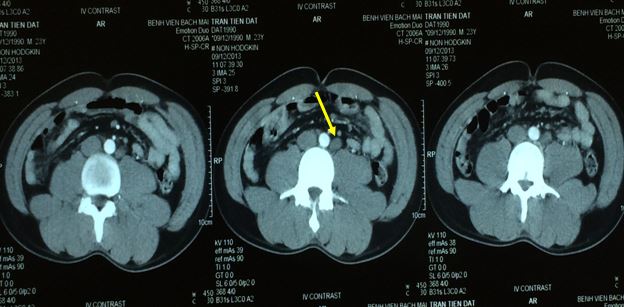

Hình ảnh hạch cạnh động mạch chủ bụng, kích thước 2-3cm.

Trên CT ổ bụng có tổn thương hạch cạnh động mạch chủ bụng 1,3cm, nghi ngờ bệnh chưa đáp ứng hoàn toàn hoặc bệnh tiến triển. Bệnh nhân được vào viện chụp PET/CT kiểm tra.

Tổn thương hạch ổ bụng còn lại trên CT sau R- CHOP x 8.

Tổn thương hạch ổ bụng hoàn toàn không hấp thu FDG.